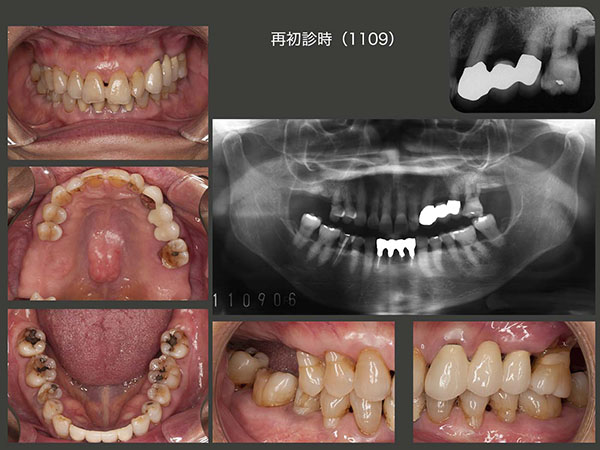

1995年10月初診.49歳女性.主訴は歯周病の予防をしたい.歯周病の治療終了後に前歯の審美性向上を期待し,歯科矯正を行った.(スライド上段中央の写真は下顎前方位の状態)96年5月,治療は一段落ついた.その後定期的にリコールに応じてもらった.スライド中・下段に95年初診時から2009年までのパノラマX線写真を示す.歯のプラークコントロールは申し分ないが,咬合力が著しく強い.それが一番の原因と思われるが,咬合支持歯で主にここで食事をしていると思われる左上7を98年8月,左上4を00年6月,右上6を06年2月にそれぞれ歯周病で失った.なお,04年5月に右下5を歯冠破折から抜髄した.下顎2〜2の前歯は,咬合力によるアブフラクションおよび歯間ブラシの過度の使用から歯がすり減ったことが原因で抜髄した.

2011年9月,上顎大臼歯部唯一の残存歯であり,かつ咬合支持歯である左上6の歯周病が進行し,10月に抜去した.現状では臼歯部は小臼歯部での咬合となるが,小臼歯だけではこの患者さんの咬合力にはとても耐えることができないと判断した.そこで,コーヌス義歯を製作することにした.コーヌス義歯は義歯を介して歯をつなぐことができるので,歯の連結固定が得られ,咬合力に対抗できる利点がある.(2次固定)また,義歯床でも咬合力を担うことができる.さらに,仕事(美容師)中に,歯を接触(TCH)しないように常に意識すること,および食事中になるべく力を入れないように努力することをお願いした.

2012年9月,片側処理のコーヌス義歯を左右に装着した.いきなり両側性設計の義歯を装着すると違和感が生じやすいので,まずは口蓋を覆わない形にしたが,11月,装着して直ぐに右上4の歯周ポケットが悪化した.そこで直ぐに固定効果を増すために左右義歯床を連結する必要に迫られた.口蓋を覆う位置を実験的に検討したが,最終的に口蓋隆起を除去し,その空いたスペースに大連結装置を付与させてもらうということで了解してもらった.13年8月,パラタルプレートを装着し,両側性設計の義歯に改変した.